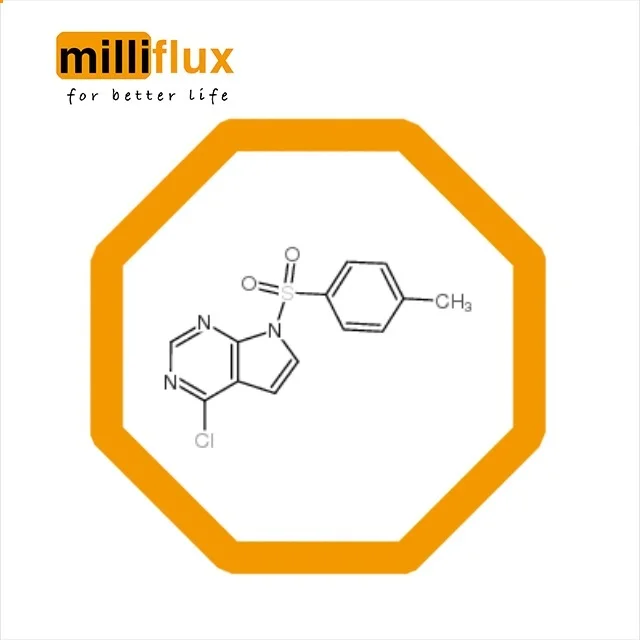

Competitive Price 4-Chloro-7-tosyl-7H-pyrrolo[2,3-d]pyrimidine 479633-63-1

Quick Details Port: Any main port in china Payment Terms: L/C,T/T,Western Union,MoneyGram Supply Ability: 10000 Kilogram/Kilograms per Month Origin: China Other Names: N/A Purity: 99min% Website: Grade: EP,USP,CP,JP Shelf life: Proper Storage Appearance: N/A CAS No.: 479633-63-1 Assay: 99.0 %min Type: pharmaceutical intermediates,Syntheses Material Intermediates Storage: Room Temperature Packing: 25kg/drum or 20kg/bag EINECS No.: N/A MF: C13H10ClN3O2S Application: Raw Intermediates Packaging Detail: 1kg/5kg/10kg/25kg/200kg or as your special request. Product Description Product Name:4-Chloro-7-tosyl-7H-pyrrolo[2,3-d]pyrimidine 479633-63-1 Density: 1.49g/cm3 Boiling Point: 505.3ºC at 760 mmHg Flash Point: 259.4ºC Refractive Index: 1.696 Company Information Packaging & Shipping FAQ Contact us